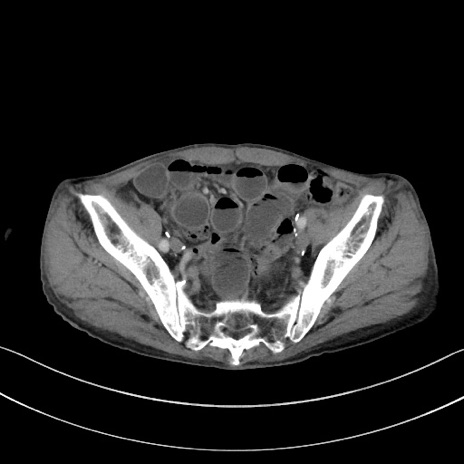

症例3(横断像)

【症例】 70歳代男性

【主訴】右鼠径部腫瘤、疼痛

【現病歴】本日朝より上記主訴あり、受診。

【既往歴】膀胱癌にて膀胱全摘、両側尿管皮膚瘻

【データ】WBC 5600、CRP 0.56